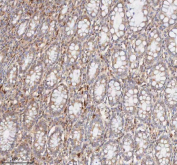

IHC staining of FFPE human colon tissue with CD127 antibody. HIER: boil tissue sections in pH8 EDTA for 20 min and allow to cool before testing.